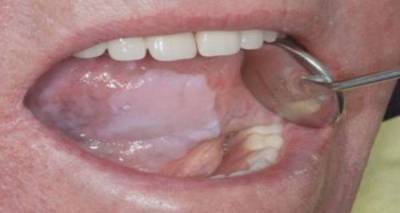

Γράφει ο Στρατιωτικός Χειρουργός Οδοντίατρος Ραϊσάκης Βασίλειος – Μάριος

Χιλιάδες Έλληνες πάσχουν σήμερα από λευκοπλακία, μια νόσο που εμφανίζεται κυρίως σε καπνιστές με τη μορφή μιας λευκής πλάκας, όπως μαρτυρά και η ονομασία της, στο βλεννογόνο του στόματος.

Ας το ξαναθυμηθούμε όλοι καπνιστές και μη καπνιστές

Μικροί και μεγάλοι